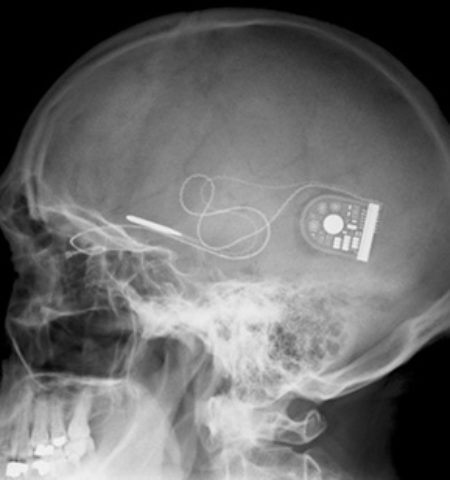

Retinal Implant Gives the Gift of Sight to Nine Blind People. 2.4k views

Blind Man Regained His Vision by Having a Tooth Implanted in His Eye 22.4k views